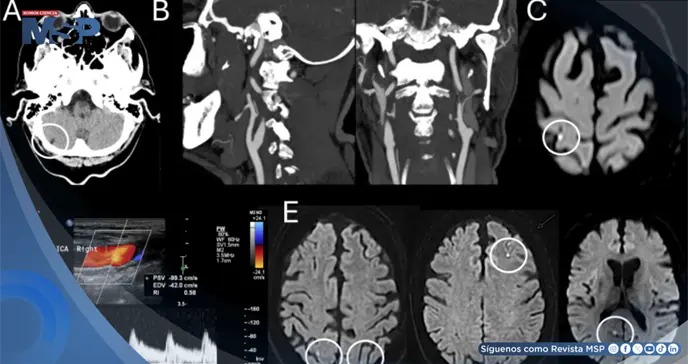

Seis meses antes, este mismo paciente había sido diagnosticado con un infarto cerebeloso derecho crónico y asintomático, sin que se identificara una fuente embólica clara. En esa ocasión, se había descartado un estado protrombótico relacionado con su tumor y se había iniciado tratamiento con un antiagregante plaquetario y estatinas.

Mientras que la tomografía computarizada inicial solo mostró el viejo infarto cerebeloso conocido, la resonancia magnética cerebral reveló el hallazgo decisivo: una pequeña lesión isquémica aguda (visible en secuencias de difusión) localizada en la circunvolución poscentral del lóbulo parietal derecho, específicamente en una zona conocida como unión parieto-occipital (PO).

Este infarto "puntiforme" o "en gota" correspondía al territorio de la arteria cerebral media.

Se diagnosticó al paciente con un accidente cerebrovascular isquémico agudo en la corteza parietal derecha (unión PO), cuya etiología final se clasificó como embólica de origen indeterminado, a pesar de exhaustivos estudios para buscar una causa.